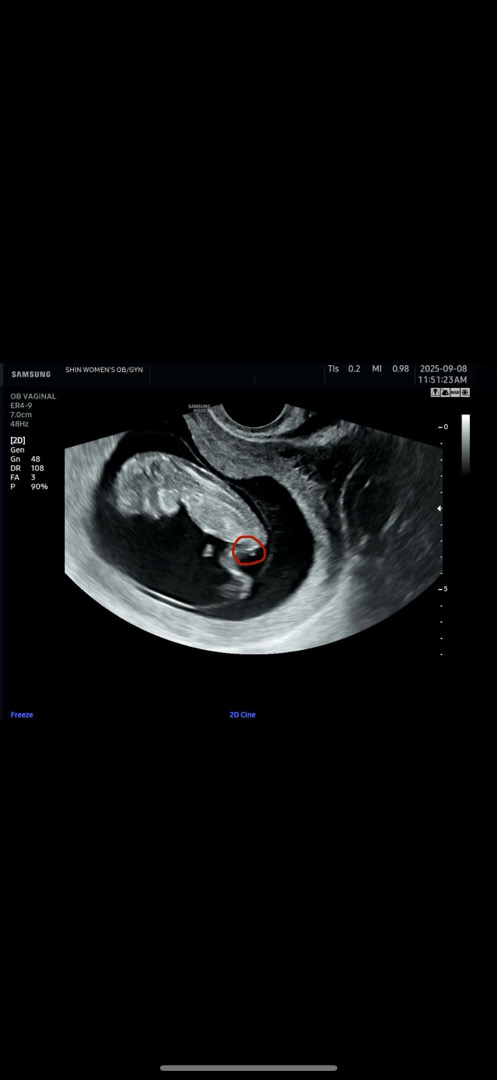

11주5일 초음파

혹시저거 뭔가요?? 탯줄인가요 아니면...